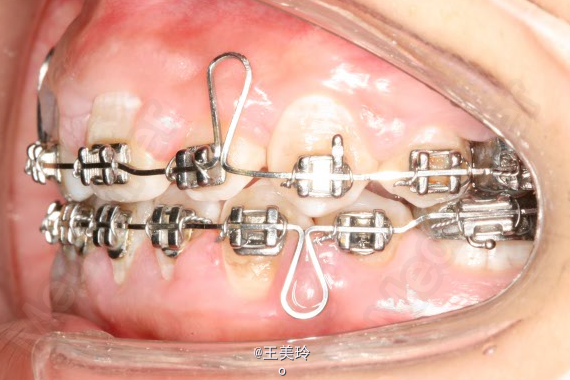

主诉:面突求矫治 既往史:无矫治史,无牙科治疗史,无外伤史,无过敏史,无口腔不良习惯,无家族遗传史 口腔检查:恒牙列,A7-B7;C7-D7。个别牙齿不齐 尖牙磨牙I类关系轻度深覆合深覆盖 下颌中线右偏约2mm 双颌前突,突面型 关节无弹响无压痛

诊断:安氏I类双颌前突 矫治计划 1.MBT矫治技术 2.拔牙矫治,拔A4B4C4D4 3.闭隙曲,J勾内收前牙 4.矫治结束后尖牙,磨牙,覆合覆盖正常 5.面型有所改善